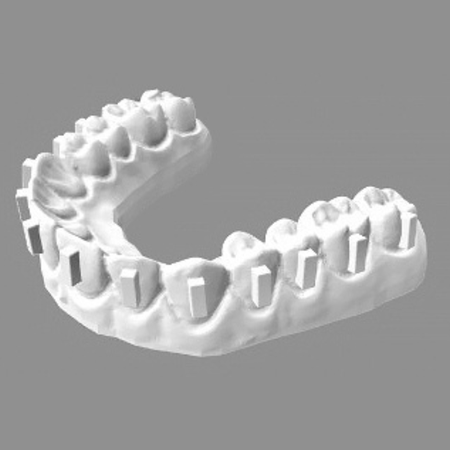

O efeito do uso de lupas odontológicas na precisão dos attachments de alinhadores e na área de adesivo remanescente após a colagem

Objetivo: Este estudo teve como objetivo avaliar se o uso de lupas odontológicas melhora a precisão na colagem de attachments em alinhadores e reduz a quantidade de resina remanescente após a colagem. Métodos: Seis modelos impressos em resina epóxi (n=14 dentes por modelo) foram criados para produzir arcadas superiores. Todos os attachments foram colados com o composto G-ænial Posterior utilizando o mesmo template de alinhador, e os protocolos diferiram quanto ao uso de lupa...